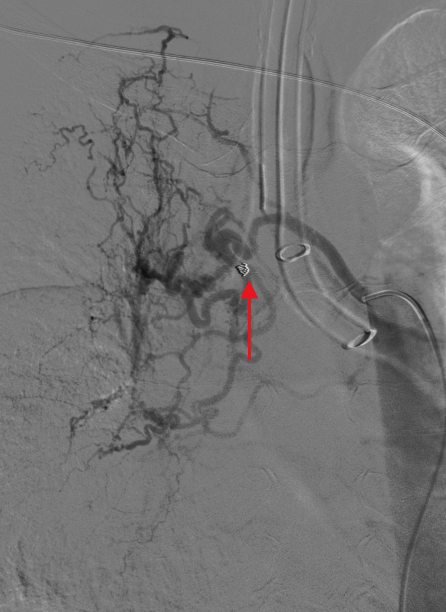

手术过程中,医疗团队规范操作。术中造影清晰显示,患者右侧支气管动脉存在明显扩张迂曲畸形,且有广泛明显的造影剂外渗出血影。随后,医生小心操作,将超选导管送至右侧出血动脉主干,采用1个44mm规格、1个43.7mm规格弹簧圈进行动脉栓塞,再运用适量明胶海绵颗粒进一步栓塞支气管动脉,直至血流停滞。再次造影确认出血影完全消失,左侧肺支气管动脉未见异常。整个手术过程顺利,术后患者恢复良好,症状平稳,最终康复出院。

▲超选导管至出血动脉主干,予弹簧圈行动脉栓塞